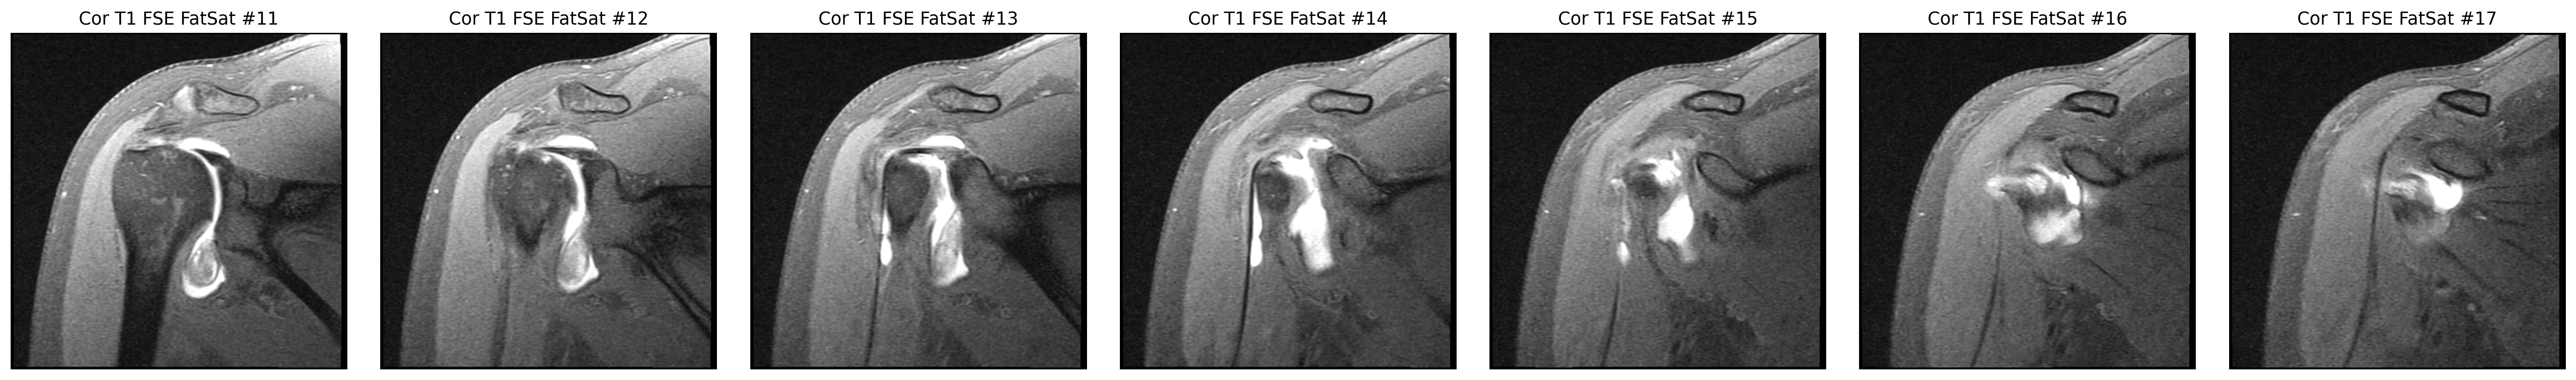

Focused coronal look at the supraspinatus footprint.

Step 1

7 MRI series and 1 fluoroscopy series were reviewed directly from the repo assets.

Step 2

The cuff finding was checked in coronal and sagittal views, while the labrum was reviewed on axial arthrogram slices.